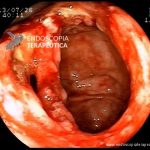

- Doença de Crohn em remissão – cicatriz